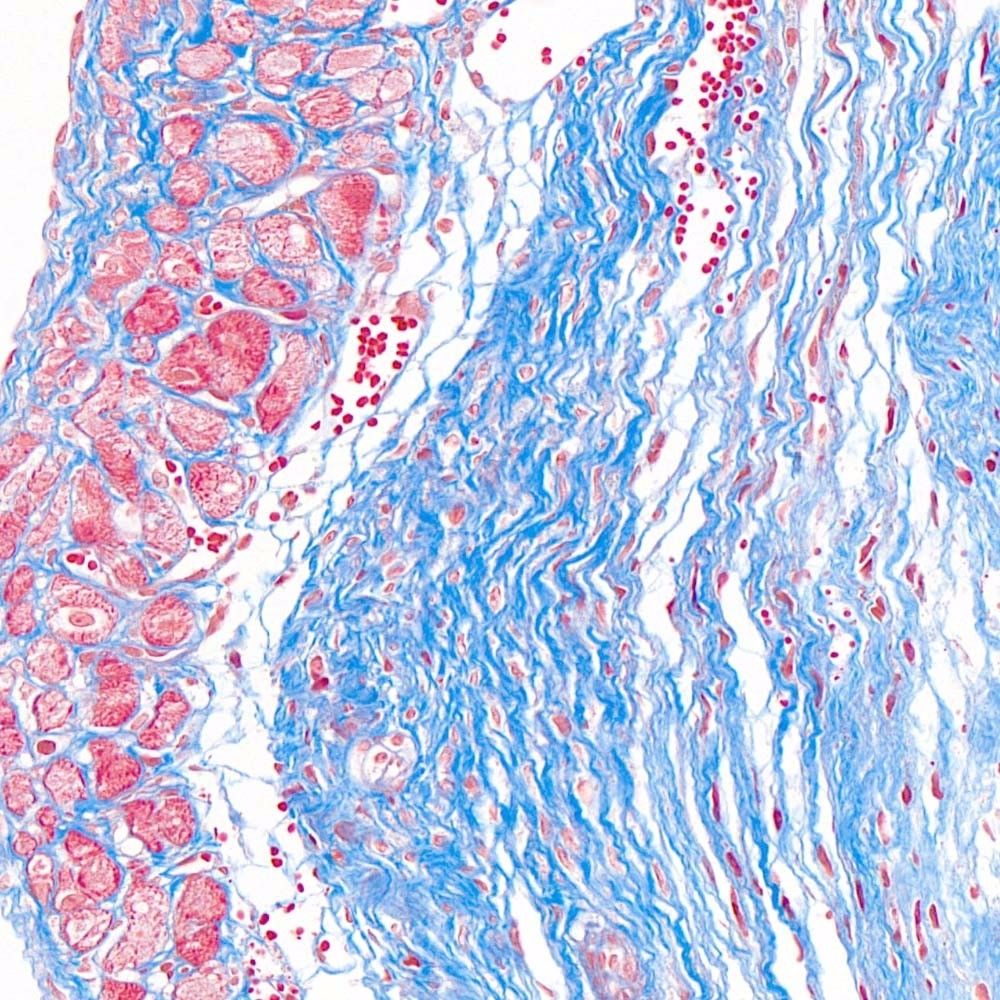

MASSON(馬松)染色實(shí)驗(yàn)過程中常見問題和解決方法由普拉特澤生物技術(shù)為大家總結(jié)分享。本文是關(guān)于MASSON染色實(shí)驗(yàn)的最后一篇介紹,前面我們深入了解了MASSON染色:原理、步驟與實(shí)例、如何進(jìn)行MASSON染色?、MASSON染色方法及其在實(shí)驗(yàn)室的應(yīng)用可以點(diǎn)擊標(biāo)題直接傳送回去學(xué)習(xí)的哦。普拉特澤生物病理檢測平臺(tái)承接MASSON實(shí)驗(yàn)外包上百例,早就為大家把實(shí)驗(yàn)過程中要踩的雷、吃的虧幫大家吃完了,現(xiàn)在我們就來看看,實(shí)驗(yàn)過程中還有哪些常見的問題和解決方法吧!

在MASSON(馬松)染色實(shí)驗(yàn)過程中,可能會(huì)遇到一些常見問題,這些問題可能會(huì)影響染色效果和結(jié)果的準(zhǔn)確性。以下是一些常見問題及其解決方法:

除了以上常見問題外,實(shí)驗(yàn)者在操作過程中還應(yīng)注意以下幾點(diǎn):首先,蘇木素用于細(xì)胞核的染色,染色時(shí)間可根據(jù)實(shí)際情況自行調(diào)整;其次,MASSON復(fù)合染色液經(jīng)磷鉬酸分化時(shí)須用顯微鏡控制,確保肌纖維和膠原纖維呈現(xiàn)正確的顏色;最后,組織固定是實(shí)驗(yàn)成功的關(guān)鍵,應(yīng)選擇合適的固定劑并控制固定時(shí)間。